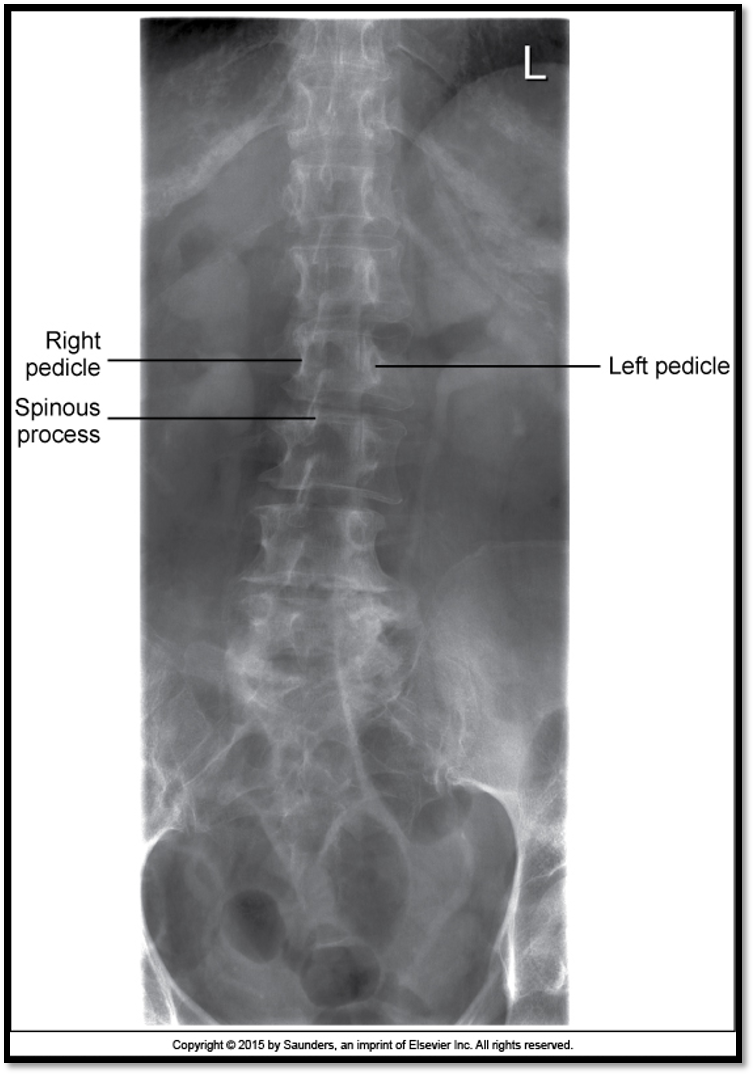

AP Lumbar Spine

A

• spinous processes are midline

• open disc spaces

• T10-S1 included

pelvis is rotated in an LPO position